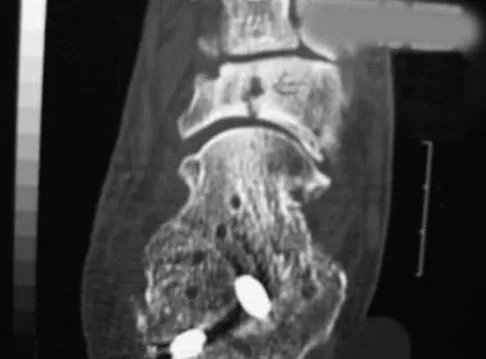

Figure 7 shows the CT scan of a 25-year-old soccer player who has had posterior ankle pain with plantar flexion for the past 2 years. Immobilization has failed to provide relief. He is ambulatory. Management should consist of

Explanation

An os trigonum is usually asymptomatic, but this accessory bone has been associated with persistent posterior ankle pain, which has been described as os trigonum syndrome. This usually affects athletes and ballerinas. Forced plantar flexion leads to impingement of the os trigonum against the posterior tibial plafond, and flexor hallucis tendinitis may develop. It may be difficult to differentiate a fractured trigonal process from the os trigonum. MRI may reveal bone marrow edema that may aid in the diagnosis of os trigonum syndrome. Steroid injections may lead to tendon rupture. The results of excision of a symptomatic os trigonum through a posteromedial or lateral approach are favorable, with a rapid return to full function. The main complication of this procedure is sural nerve injury with a lateral approach. Hedrick MR, McBryde AM: Posterior ankle impingement. Foot Ankle Int 1994;15:2-8.